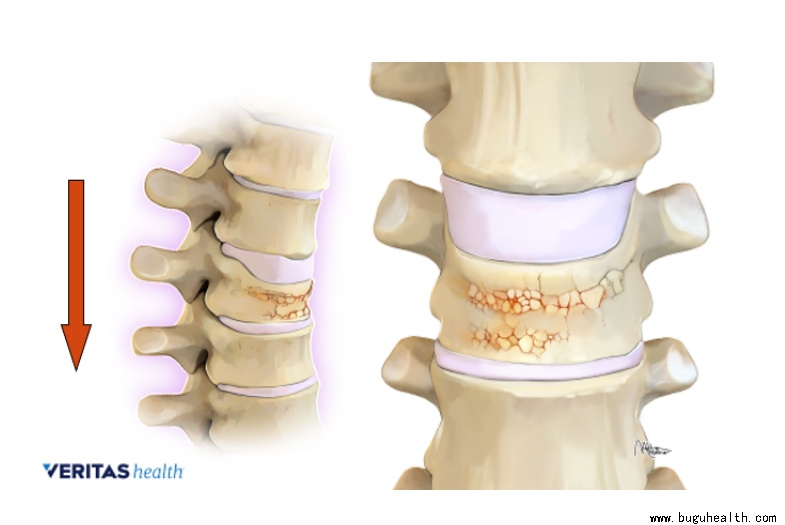

骨质疏松的骨质,就好像木质建筑被蛀虫啃食得千疮百孔,强度降低自然更容易断裂。由于脊柱主要承受着躯干的重量,受重力作用向下传递,因此最常见的骨折类型就是压缩性骨折。表现为椎体前柱的塌陷,后柱相对完整,可引起局部的后凸。